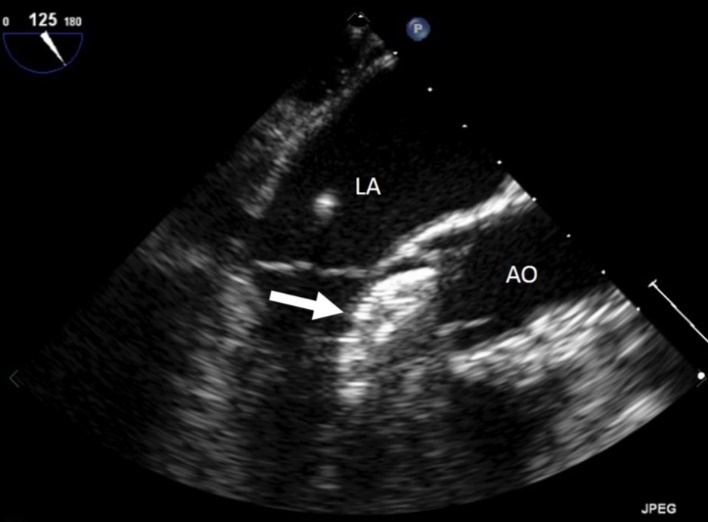

On examination, her heart rate was 71 beats per minute regular, blood pressure was 143/80 mm Hg, air saturation was 96% breathing ambient air and no fever. Jugular veins were not engorged. S1 and S2 were normal. There was a grade 3/6 ejection systolic murmur at right upper parasternal area. 24 hours ECG monitoring showed sinus rhythm. The neurological and pulmonary examination was normal. She underwent immediate transthoracic echocardiography and subcostal view showed a left-right shunt at the interatrial septum. Further evaluation revealed that the device embolized to the left ventricle and was lying in the left ventricular outflow tract with the distal extremity crossing the aortic ring. The device was displaced longitudinally with an important effect of stenosis. (Figure 1), (Figure 2). The entrapped device induced mechanical obstruction of the left ventricular outflow tract with a maximum/minimum gradients of 64/42 mmHg. The left ventricular function and size were normal. The mitral valve was normal with a minimal regurgitation. The right ventricle was mildly enlarged with normal function. The tricuspid valve function was normal. No pericardial effusion was detected. There was no gross thrombus deposition over the device in echography and no vegetation was detected anywhere.

Figure 1.Entraped Amplatzer ASD closure device in the left ventricular outflow tract. LA : left atrium, AO : aorta, arrow : ASD closure device.